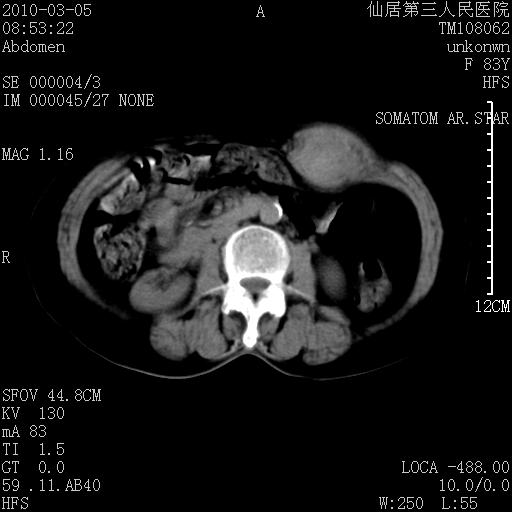

标题: CT24879:腹直肌病变。在线等。 [打印本页]

标题: CT24879:腹直肌病变。在线等。

女性,83y,腹痛一周。

考虑:左侧腹直肌神经纤维瘤可能

神经纤维瘤—伴有出血?

有无外伤,血肿或韧带样瘤

考虑左侧腹直肌血肿,肿瘤性病变待排。

增强看看,mfh可能性大,次之可考虑血肿、bfh、转移瘤、神经纤维瘤、侵袭性韧带样纤维瘤等。肝内钙化灶,右肾结石。

血肿,纤维瘤,子宫内膜异位都有可能。